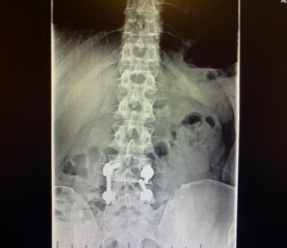

I came to HSS Stamford with broken hardware from a failed spinal fusion with another hospital. I was very reluctant as I wasn’t having good experiences elsewhere for my pain. Dr. Evan Sheha went over my imaging and took more time speaking with me than my previous three doctors combined. He listened. From my complaints, Dr. Sheha followed up with injections to make sure a hardware removal would actually help. It did!

Dr. Sheha’s wonderful assistant Viviane then set up surgery and here we are. Five weeks out living my life again! This doctor is up and coming and the best advice I can give is get him while you can! You won’t be disappointed. Set up an appointment as this is your life and your health. Dr. Sheha won’t let you down!